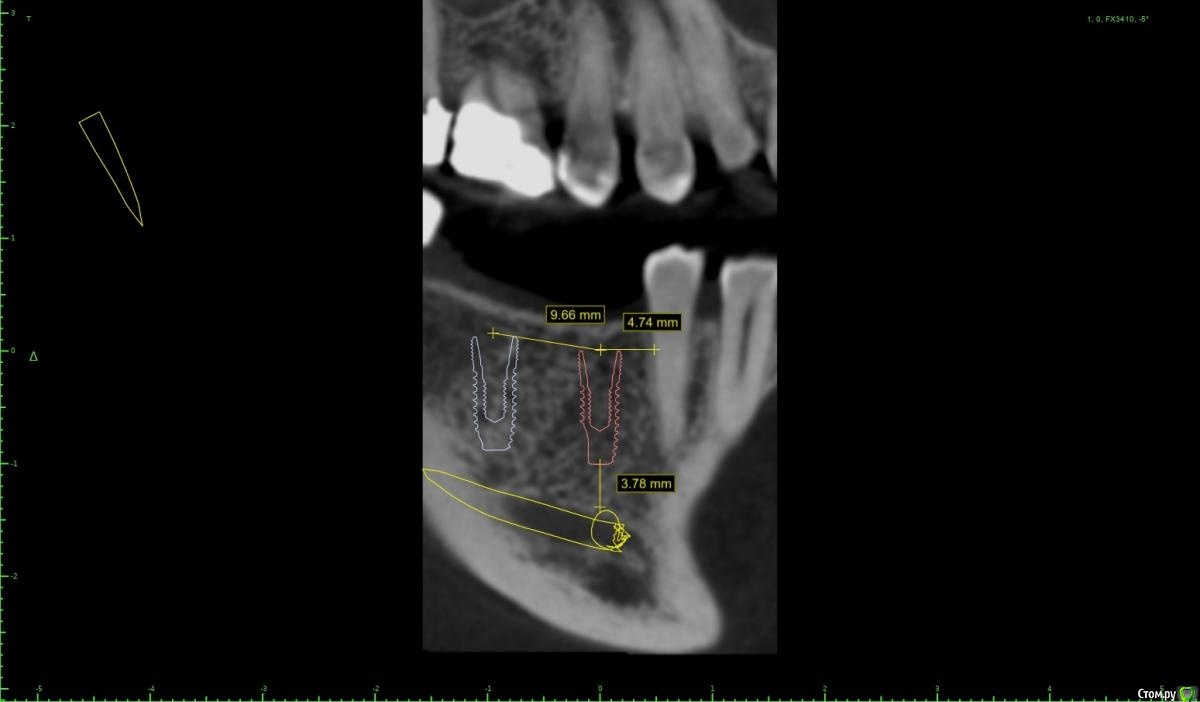

Женька Опубликовано 28 ноября, 2020 Поделиться Опубликовано 28 ноября, 2020 (изменено) Приветствую коллеги. В общем три недели назад 07.11.20 установил пациентке 2 имплантата в позиции 45-46. Гребень по ширине был около 6.5мм в области 4.5 и около 7.2мм в области 4.6 (с учётом заглубления на 1.5-2мм). Это была наверное первая имплантация во время которой я чувствовал себя спокойно и расслабленно. Всё прошло хорошо, немного покопался с непосредственным введением имплантатов, тк никак не хотели топиться на нужные 1.5мм. Поэтому пробовал методику с выкручиванием на пару витков и снова закручиванием. Особого толку не получил, потому взял финальную фрезу и чуть углублял ложе. Так несколько раз, тк боялся всё-таки немного что задену менталис и нлн. Ввиду того, что биотип у пациентки тончайший и язычно было совсем-совсем тонко - заглушки и швы. Назначил нпвс, ванны хг, аб терапию. Но на утро следующего дня пациентка сказала, что чувствует себя шикарно, решили что нпвс оставим, а аб терапию применять не будем (и грешу что в этом мою ошибка).Через неделю сняли швы, всё отлично.Спустя два дня после снятия начались какие-то "костные" боли, как говорит пациентка в области 4.5 импланта. Которые то отпускают, то снова наплывают. На 4.4 есть дефект твердых тканей (на фото виден), но судя по всему беспокоит не он .Пальпация вестибулярно в проекции 4.5 импланта болезненна, небольшая гиперемия, отёка нет. Гигиену пациентка запустила, тк боялась туда залезать и чистить. Снимки прилагаю первые два от 07.11, два последующих 28.11. Ну и внутри ротовые день операции и сегодняшние числа.Похоже 4.5 на выход? своими "туда-сюда" наверняка я нагрел всё что можно... снова расстройство в той работе, где накосячить предельно сложно... Добавка: пить аб ведь сейчас уже бесполезно? Изменено 28 ноября, 2020 пользователем Женька Ссылка на комментарий

колесников Опубликовано 28 ноября, 2020 Поделиться Опубликовано 28 ноября, 2020 (изменено) Имплант 13 мм? Зачем? При планировании видно, что он упирается апексом в кортикалку. По этому и поставить не могли сразу. Торк 45. Если имплант плотно контактирует с компактной пластинкой,она резорбируется окончато,со всеми вытекающими. Стоило выбрать имплант 8.5мм. Если притопили имплант,зачем поставили заглушку? Имплант зарастёт придётся выпиливать ,откапывать заглушку,ломать то что наросло непосильным трудом. Хороший торк-ставьте рабочий фдм. Сомнения-мелкий фдм или заглушка +1. Рекомендую сделать контрольный кт и поставить фдм Изменено 28 ноября, 2020 пользователем колесников 5 Ссылка на комментарий

Женька Опубликовано 29 ноября, 2020 Автор Поделиться Опубликовано 29 ноября, 2020 Я бы сейчас сделала три вещи :дала курс антибиотика шикарной женщине,гигиену навела бы во рту или хотя бы в этой области,депульпировала премоляр.Чтобы прикрыться со всех сторон. Выждать. Вынуть всегда успеется.А потом.. может,там уже формики просятся?Три недели, не рановато ли? По поводу премоляра, терапевта напрягу. А на каком режиме Вы закручиваете/выкручиваете?20оборотов на торке 30, далее руками динамометрическим ключом. Имплант 13 мм? Зачем? При планировании видно, что он упирается апексом в кортикалку. По этому и поставить не могли сразу. Торк 45. Если имплант плотно контактирует с компактной пластинкой,она резорбируется окончато,со всеми вытекающими. Стоило выбрать имплант 8.5мм.Импланты 10мм каждый, разметка на планировании - глубина препарирования с учётом заглубления. Проблема то как раз в области 4.5 импланта, там нет такого контакта с кортикой апикально, а область шейки хорошо развальцевал кортикальной фрезой. 4.6 где как раз контакт кортикальный спокоен. Если притопили имплант,зачем поставили заглушку? чтобы избежать проблем как в предыдущем моём случае, где тоже было тонко язычно. Потому хотел на этапе раскрытия работать с десной и язычно перемещать объём. http://forum.stom.ru/topic/40254-otsrochennaia-implantatciia/ Сомнения-мелкий фдм или заглушка +1. что значит заглушка +1? Если сейчас залезть и выкрутить заглушки не велики ли риски прокручивания имплантата...ведь на 3-5 недели самая большая потеря первичной стабильности происходит. Ссылка на комментарий

Женька Опубликовано 14 декабря, 2020 Автор Поделиться Опубликовано 14 декабря, 2020 (изменено) Наконец-то получил КТ от пациентки...Боли значительно уменьшились, практически не беспокоит... Коллеги, что думаете? Я так понимаю это уже не фон от титана? и вердикт всё-таки один? Сам склоняюсь всё-таки более к понаблюдать. Вестибулярно конечно очень тонко Толщина была ~ 6.7мм Изменено 14 декабря, 2020 пользователем Женька Ссылка на комментарий

Irouil Опубликовано 14 декабря, 2020 Поделиться Опубликовано 14 декабря, 2020 Ну и где тут язычно передавленная кортикалка? Меня смущает только картина в области верхушки симптомного винта, ну и заглубление Я бы дождался уже срока интеграции Ссылка на комментарий

Женька Опубликовано 14 декабря, 2020 Автор Поделиться Опубликовано 14 декабря, 2020 Ну и где тут язычно передавленная кортикалка? Меня смущает только картина в области верхушки симптомного винта, ну и заглублениеНе знаю, я про язычную кортику не говорил. Меня тоже смущает... и в области соседа такого фона (а это не фон я уверен) нет... А с заглублением что не так? по прицелам там 1.5-2мм, на кт почему-то этих мм вообще нет и как будто крестально стоят Ссылка на комментарий